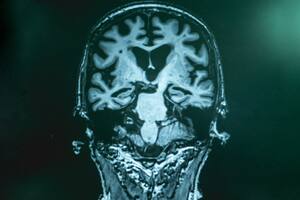

Una de las pocas certezas es que los enfermos de alzheimer presentan unas placas de proteínas, llamadas amiloides, que se forman alrededor de las neuronas y las destruyen.

¿Pero estas placas representan la principal causa? ¿O la consecuencia de otra patología? Es la principal duda de los científicos. Según la teoría de la “cascada”, el alzheimer se debe a la formación de estas placas.

Un estudio publicado este jueves en la revista Nature Neuroscience pone en duda el rol de las placas de proteínas y defiende la hipótesis de que en realidad el alzheimer surgiría en el interior de las neuronas, en lugar del exterior.

Esta publicación, realizada a partir de análisis en ratones modificados genéticamente para introducir el equivalente del alzheimer, apunta a una posible disfunción de las lisosomas, unos orgánulos celulares que sirven para “digerir” aquellos componentes inútiles o degradados.